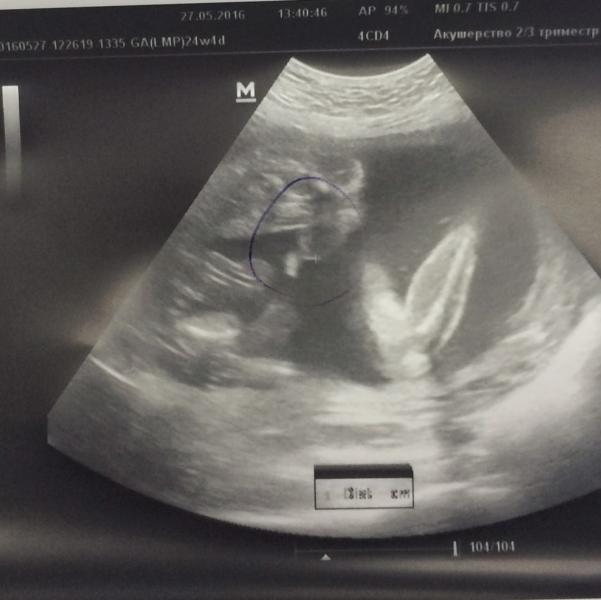

post image

Ходили с мужем в Медок к врачу Яссин

Подтвердили мальчика 👶🏼🌶

716 грамм счастья ❤️ все органы на месте, ручки ножки ушки

Личико не увидели, отвернулся 😔

Плацента поднялась,ура 🤘🏼

27.05.2016